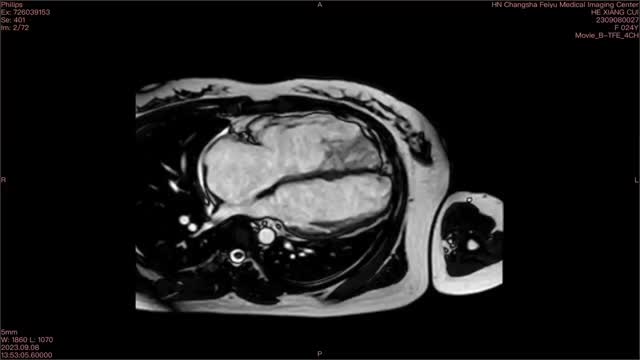

A previously healthy 25-year-old female presented to the emergency department with 5 h of palpitations and lightheadedness. Upon admission, the electrocardiogram (ECG) showed sustained ventricular tachycardia (VT) of left bundle branch block (LBBB) morphology with superior axis (Fig. 1A). The VT episode was terminated by intravenous amiodarone. Subsequent ECG after cardioversion revealed T wave inversion in all precordial leads and epsilon wave in leads V2 and V3 (Fig. 1B). Of note, her father died suddenly at the age of 38. Further cardiac magnetic resonance (CMR) revealed global hypokinesia in the free wall of the right ventricle (RV), as well as regional hypokinesia in the left ventricular apical wall (Fig. 1C, D, Supplement data Video 1). Notably, right ventricular ejection fraction was only 3%. Moreover, evidence of myocardial fibrosis was observed at the apex of the left ventricle (LV), with no such findings noted in the RV (Fig. 1E, Supplement data Video 2). Genetic testing revealed a mutation in the PKP2 gene. Based on the findings mentioned above, the diagnosis of arrhythmogenic right ventricular cardiomyopathy (ARVC) with LV involvement was established. The patient was started on metoprolol and was advised to undergo implantable cardioverter defibrillator (ICD) implantation.